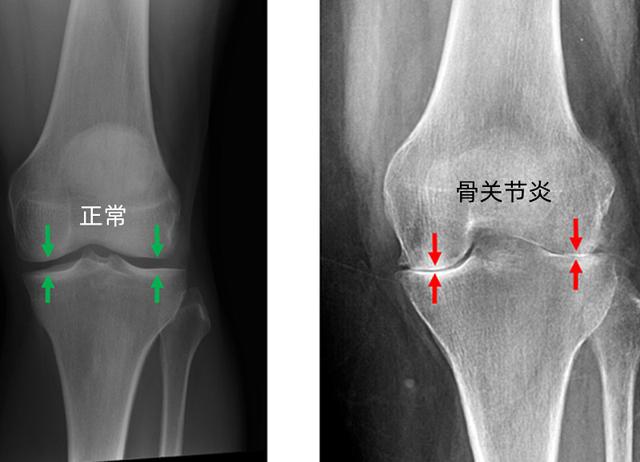

关节炎引起的膝关节疼痛膝骨关节炎的典型症状是关节疼痛和僵硬,同时伴有活动范围受限。它的疼痛来源于关节中的弹性软骨损失,继而膝关节软骨变薄,关节表面变粗糙,骨头和骨头摩擦,膝盖不能像正常情况下那样平稳地活动,患者会感到疼痛,僵硬和炎症。通过X光通常能发现软骨的损失,但关节炎疼痛的轻重和表现形式多种多样,具体症状取决于关节退化的程度和性质,还有患者的体重,体质以及对疼痛的个人感受。

硬肿胀:关节边缘的骨头向外生长,形成骨刺,也称为骨质增生,骨刺通常是关节退化及骨关节炎的表现,当关节的骨与软骨遭受了一定程度的损失,人体处于自我修复的目的,骨刺就相当于骨头上的疤。软肿胀:当关节发炎时产生多余的液体时,称为膝盖积液或积水。如果发现以上迹象,建议尽快就医,骨关节炎一旦发生不可逆,早诊断早治疗非常重要。